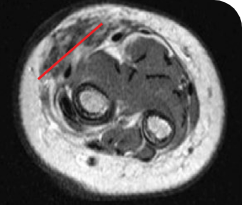

PEDIATRIC CANCER PATIENT WITH METASTATIC DISEASE

BASELINE BEFORE VITRAKVI

AFTER 6 MONTHS ON VITRAKVI

5-MONTH-OLD WITH INFANTILE FIBROSARCOMA5

PATIENT CASE:

INFANTILE FIBROSARCOMA

OF SOFT TISSUE1

- 5-month-old with IFSa

- Progression after chemotherapy

- Confirmed PRa after 4 cycles of VITRAKVI® (larotrectinib)

- Referred for definitive limb-sparing surgery after 6 cycles

of VITRAKVI; achieved pCRa,b

Clinical presentation1

- Diagnosed with localized IFS of the soft tissue of the forearm

Prior treatments and outcomes1

- Patient progressed after 2 cycles of vincristine and actinomycin D

- He was subsequently placed on vincristine, actinomycin D, and cyclophosphamide; however, his response remained inadequate to allow for limb-sparing surgery

Testing1

- ETV6a-NTRK3a fusion identified with DNAa NGSa panel testing

VITRAKVI treatment1

- VITRAKVI 100 mg twice daily orally

Response to VITRAKVI1

- Patient achieved a confirmed partial response after 4 cycles of VITRAKVI with a 45% reduction in tumor burden

- Following 6 cycles of VITRAKVI, the patient was referred for definitive limb-sparing surgery

- Pathology revealed a complete pathologic response and clear resection margins with scar tissue noted

Reduction in tumor burden1

MRIa imagery of the brain. Red line indicates the maximum dimension.1

aMRI, magnetic resonance imaging.

Pre- and post-treatment imaging, by DuBois SG et al, is licensed under CC BY 4.0.